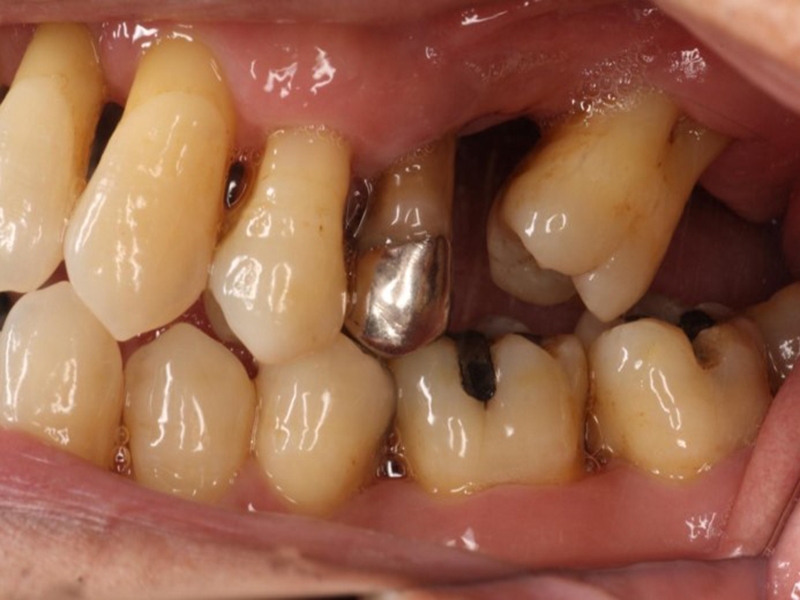

矯正開始前